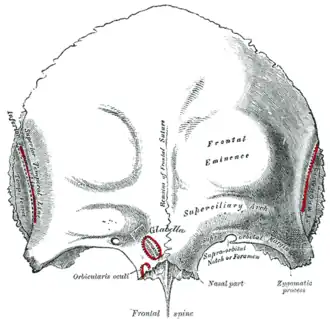

Frontal bone. Outer surface. (The Pars orbitalis is the bottom third.) | |

The orbital or horizontal part of the frontal bone (pars orbitalis) consists of two thin triangular plates, the orbital plates, which form the vaults of the orbits, and are separated from one another by a median gap, the ethmoidal notch.

Surfaces

- The inferior surface of each orbital plate is smooth and concave, and presents, laterally, under cover of the zygomatic process, a shallow depression, the lacrimal fossa, for the lacrimal gland; near the nasal part is a depression, the fovea trochlearis, or occasionally a small trochlear spine, for the attachment of the cartilaginous pulley of the obliquus oculi superior.

- The superior surface is convex, and marked by depressions for the convolutions of the frontal lobes of the brain, and faint grooves for the meningeal branches of the ethmoidal vessels.